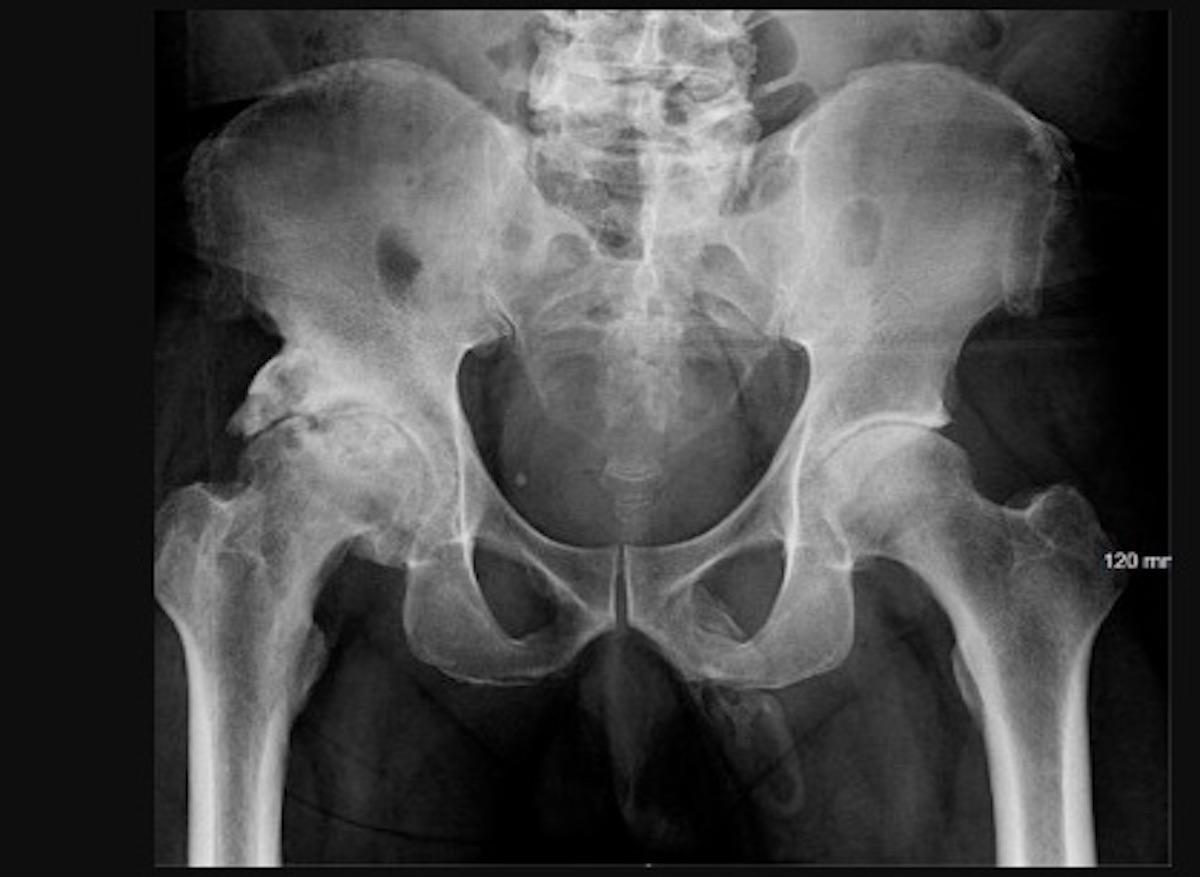

Tout commence quand le sexagénaire tombe sur les fesses sur le trottoir cet été. Des patients l’aident à se relever. S'il parvient à remarcher, cette chute déclenche une douleur lancinante au niveau de son genou gauche. Cette dernière ne disparaissant pas, il se décide à aller consulter aux Urgences de l’hôpital Lincoln à New York. Après avoir écouté son récit, les médecins effectuent une radio pelvienne. Ils découvrent alors avec stupeur que la totalité du corps du pénis (composé des corps érectiles permettant l’érection) est en train de s’ossifier.

"Une simple radiographie aux rayons X a montré une ossification pénienne de la totalité du corps du pénis qui pourrait être secondaire à la maladie de Lapeyronie", écrivent les auteurs de l’article. Malgré cet inquiétant diagnostic, le patient décide de quitter l’hôpital et disparaît dans la nature, déplorent les spécialistes. Impossible donc de lui faire passer des examens complémentaires, de réaliser une biopsie de la masse calcifiée ou même d’organiser un suivi médical.